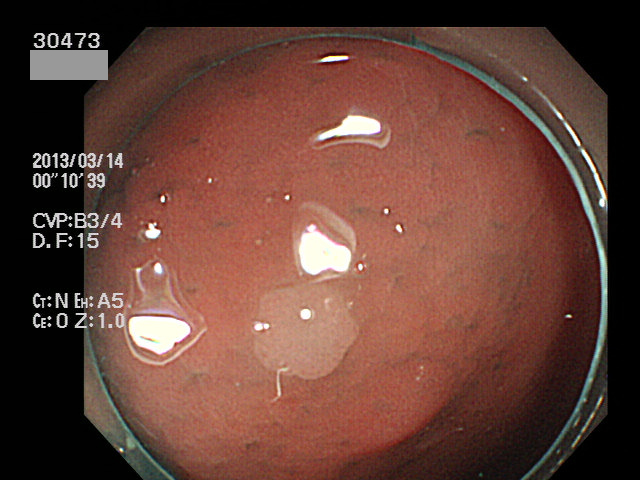

直腸やS字結腸の「外観が過形成ポリープと区別できない」小さなポリープが病理で腺腫と診断されることが時々あります。当院HPで掲載している以下の病変は、その典型です。一見すると「普通の直腸・過形成ポリープ」なのですが実は癌化の直前の病変(High grade Adenoma)でした。